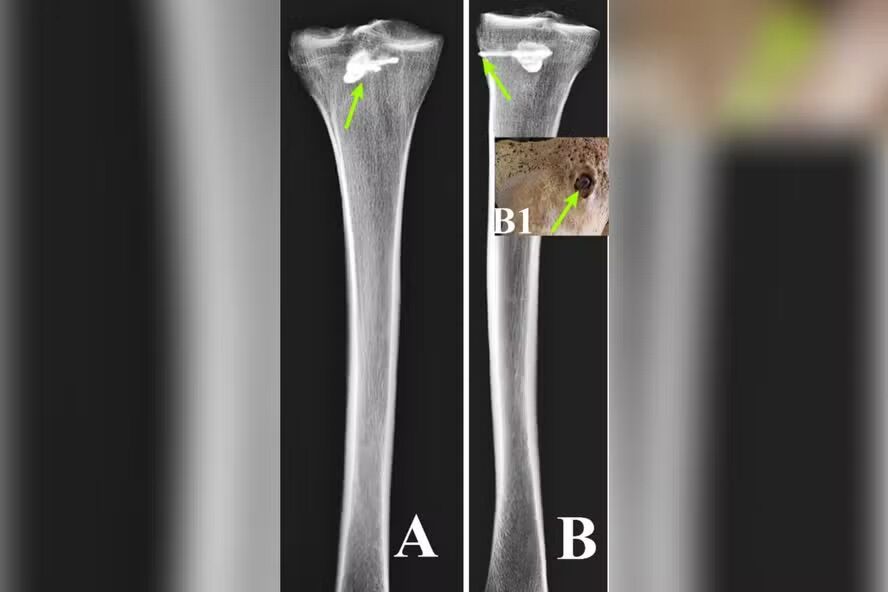

Examinations with fluorescent X-rays and computerized tomography confirmed that it was a three-bladed arrow, approximately 44 millimeters long and 15 millimeters wide, typical of Parthian armory, describes the .

The bone around the object showed signs of healing, indicating that the man survived for some time after impact, although it is not possible to determine for how long.